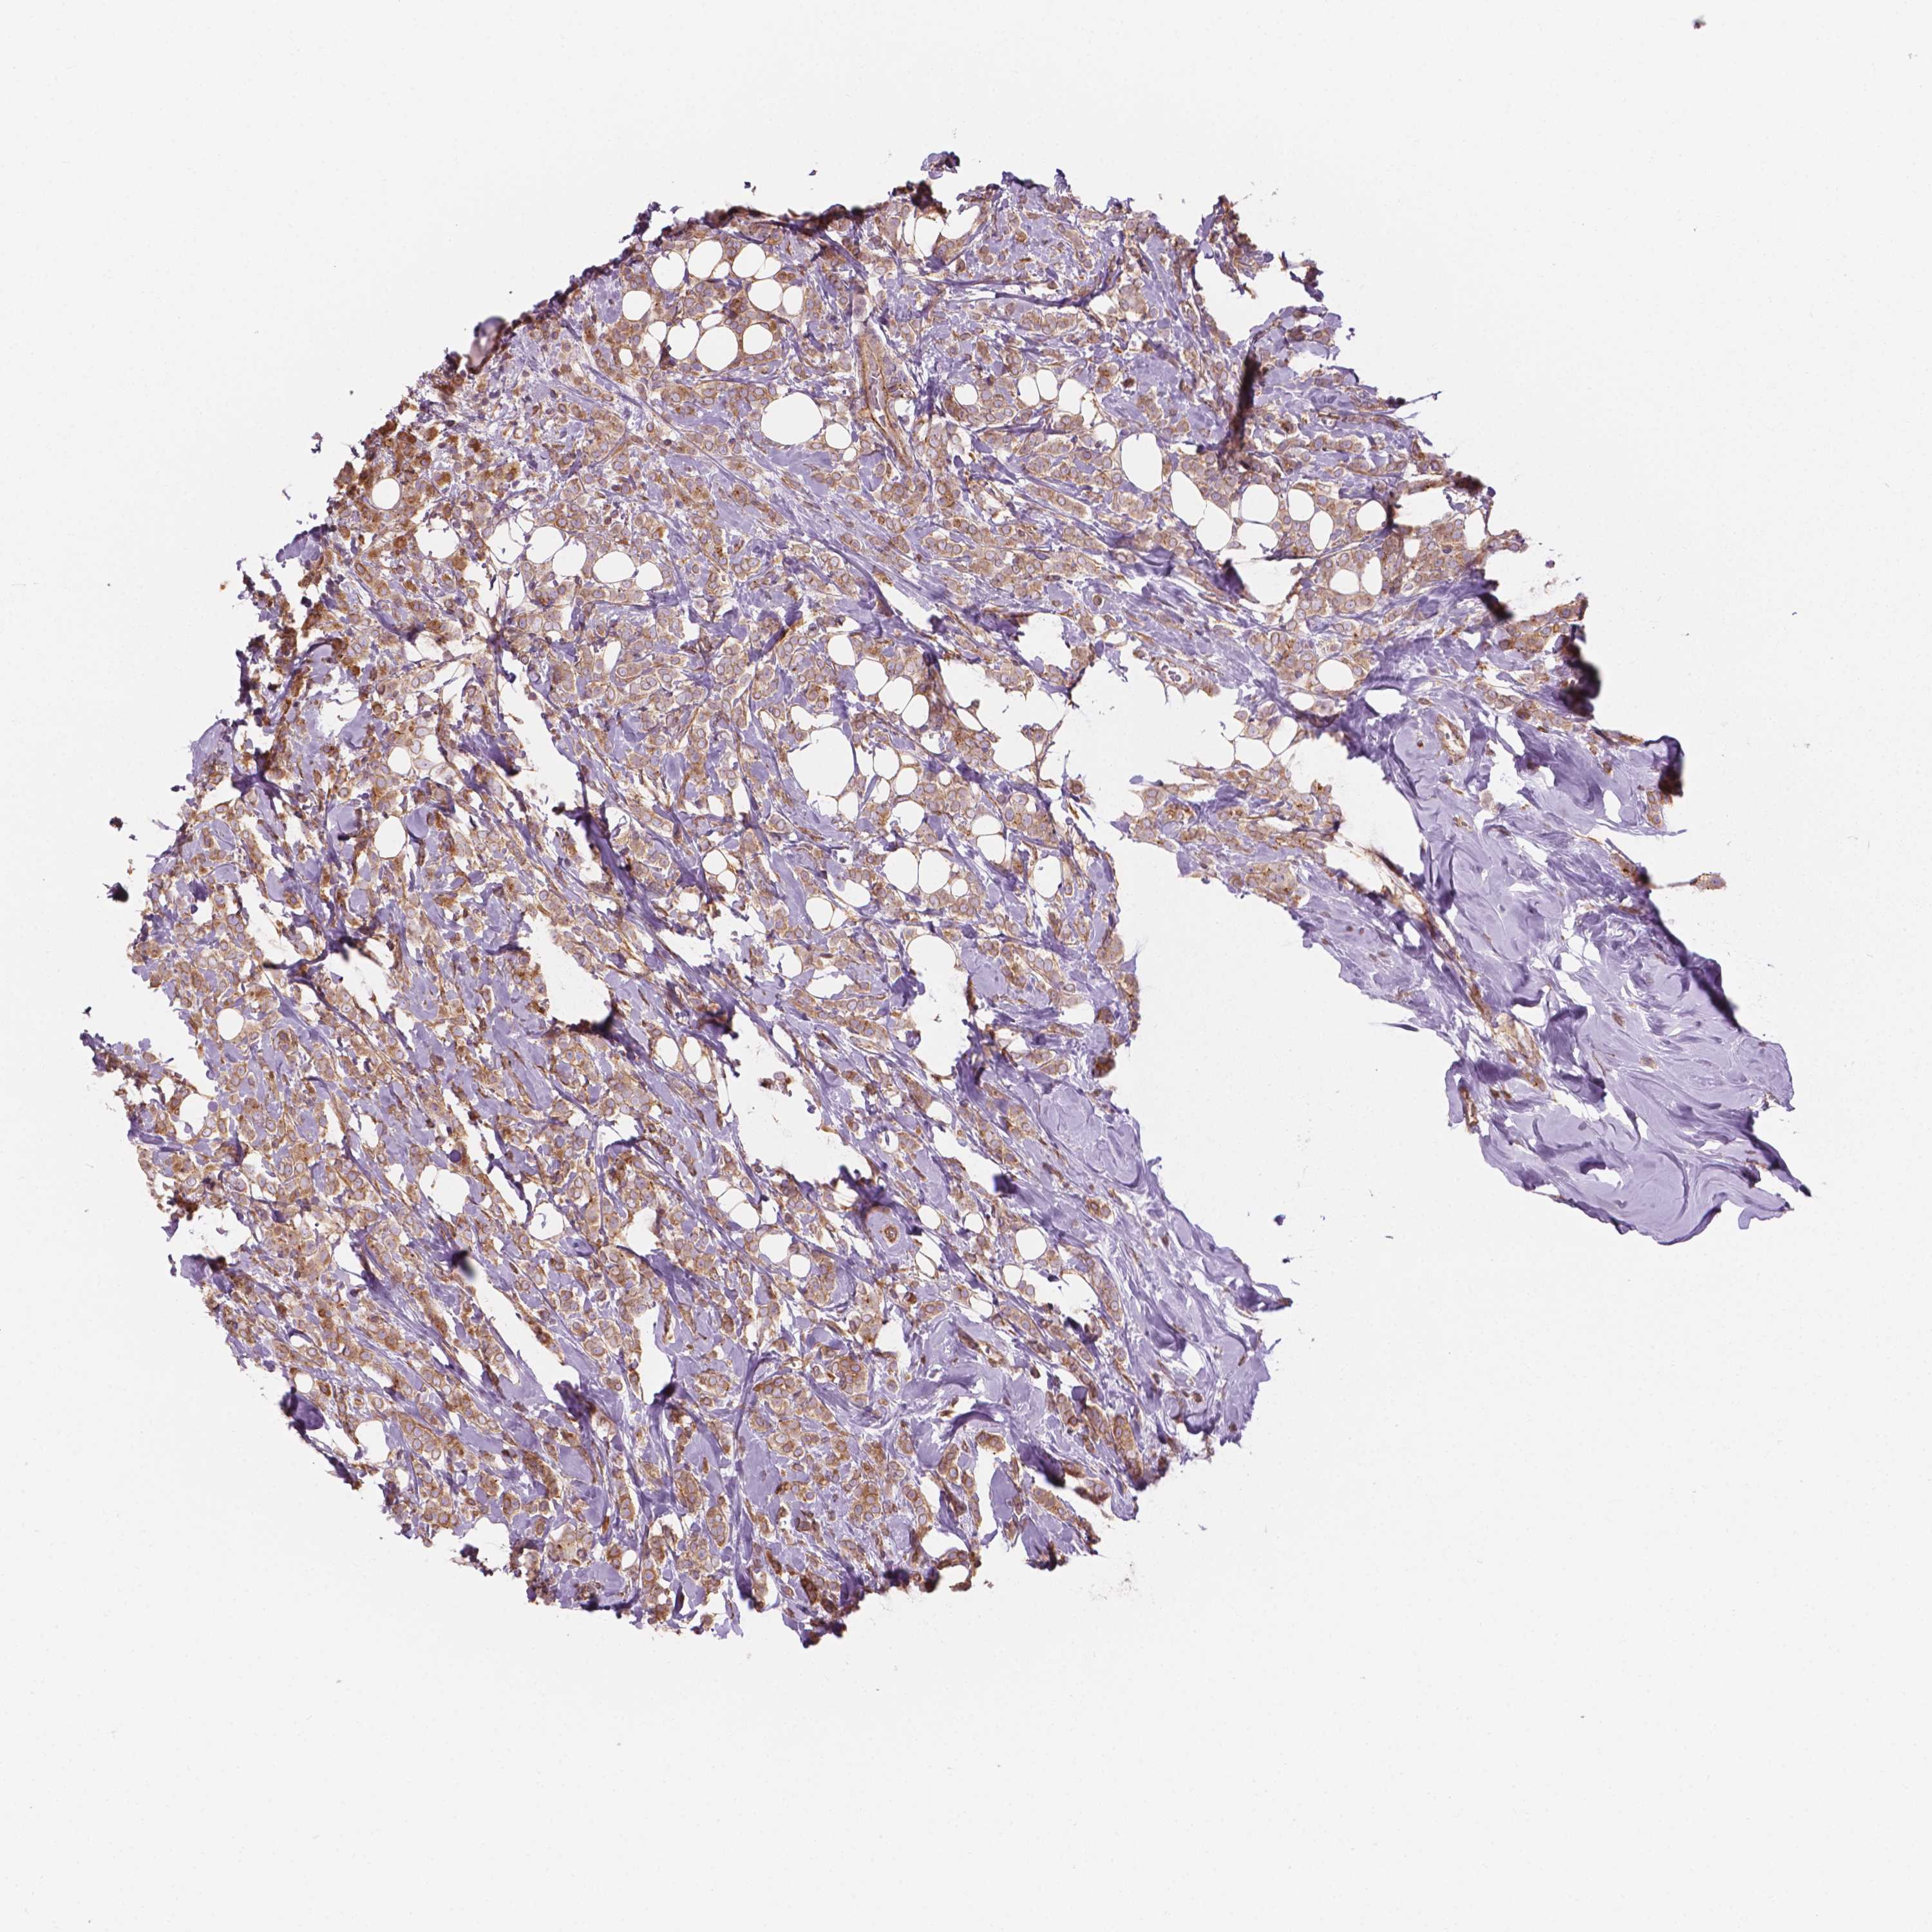

CANCER BREAST CANCER Show tissue menu

BRCA TCGA BRCA VALIDATION PROTEIN EXPRESSION